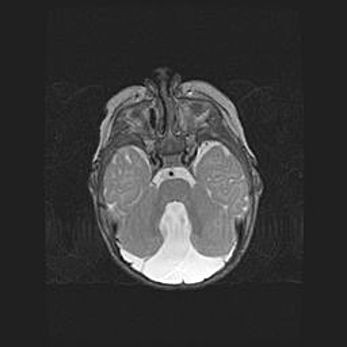

Наружная гидроцефалия с возможной атрофией височных областей.

Возраст: 28 дней

Вес: 3670 г

Пол: мужской

Окружность головы: 38 см

Срок гестации: 40 недель

Гидроцефалия головного мозга у новорожденных – это заболевание, которое характеризуется скоплением избыточного количества спинномозговой жидкости в желудочковой системе головного мозга в результате затруднения её перемещения от места выработки к месту поглощения в кровеносную систему или вследствие нарушения абсорбции. При открытой наружной форме гидроцефалии у новорожденных расширяются и переполняются субарахноидные пространства.

При нормотензивных  формах,  которые,  как  правило,  являются  следствием  перенесенных ишемических  повреждений  паренхимы  мозга,  возможно  сочетание микроцефалии  с нормотензивной гидроцефалией. В основе данных изменений лежит атрофия больших полушарий с преимущественной  локализацией  в  лобно-височных  областях.